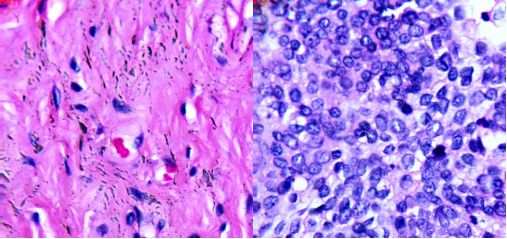

1.1.显微高光谱在肿瘤组织检测的应用

医学高光谱图像将二维空间图片与一维光谱信号合并为一个三维数据立方体。结合光谱和成像技术,医学高光谱图像的本质是反映材料以及在分子级别的电磁波下如何吸收和反射光线。它不仅包括丰富的空间信息,更包含许多称之为光谱特征的连续窄波段,这样能够准确地区分不同的血细胞。目前,医学高光谱成像技术已应用于舌肿瘤、肠道缺血及癌症、出血性休克、医疗食品安全以及其它诊断学的检测、/p>

(a)100X宫颈癌非肿瘤切片?b)100X宫颈癌肿瘤切牆/p>

(a)40膀胱癌非肿瘤切片;(b)40膀胱癌肿瘤切片